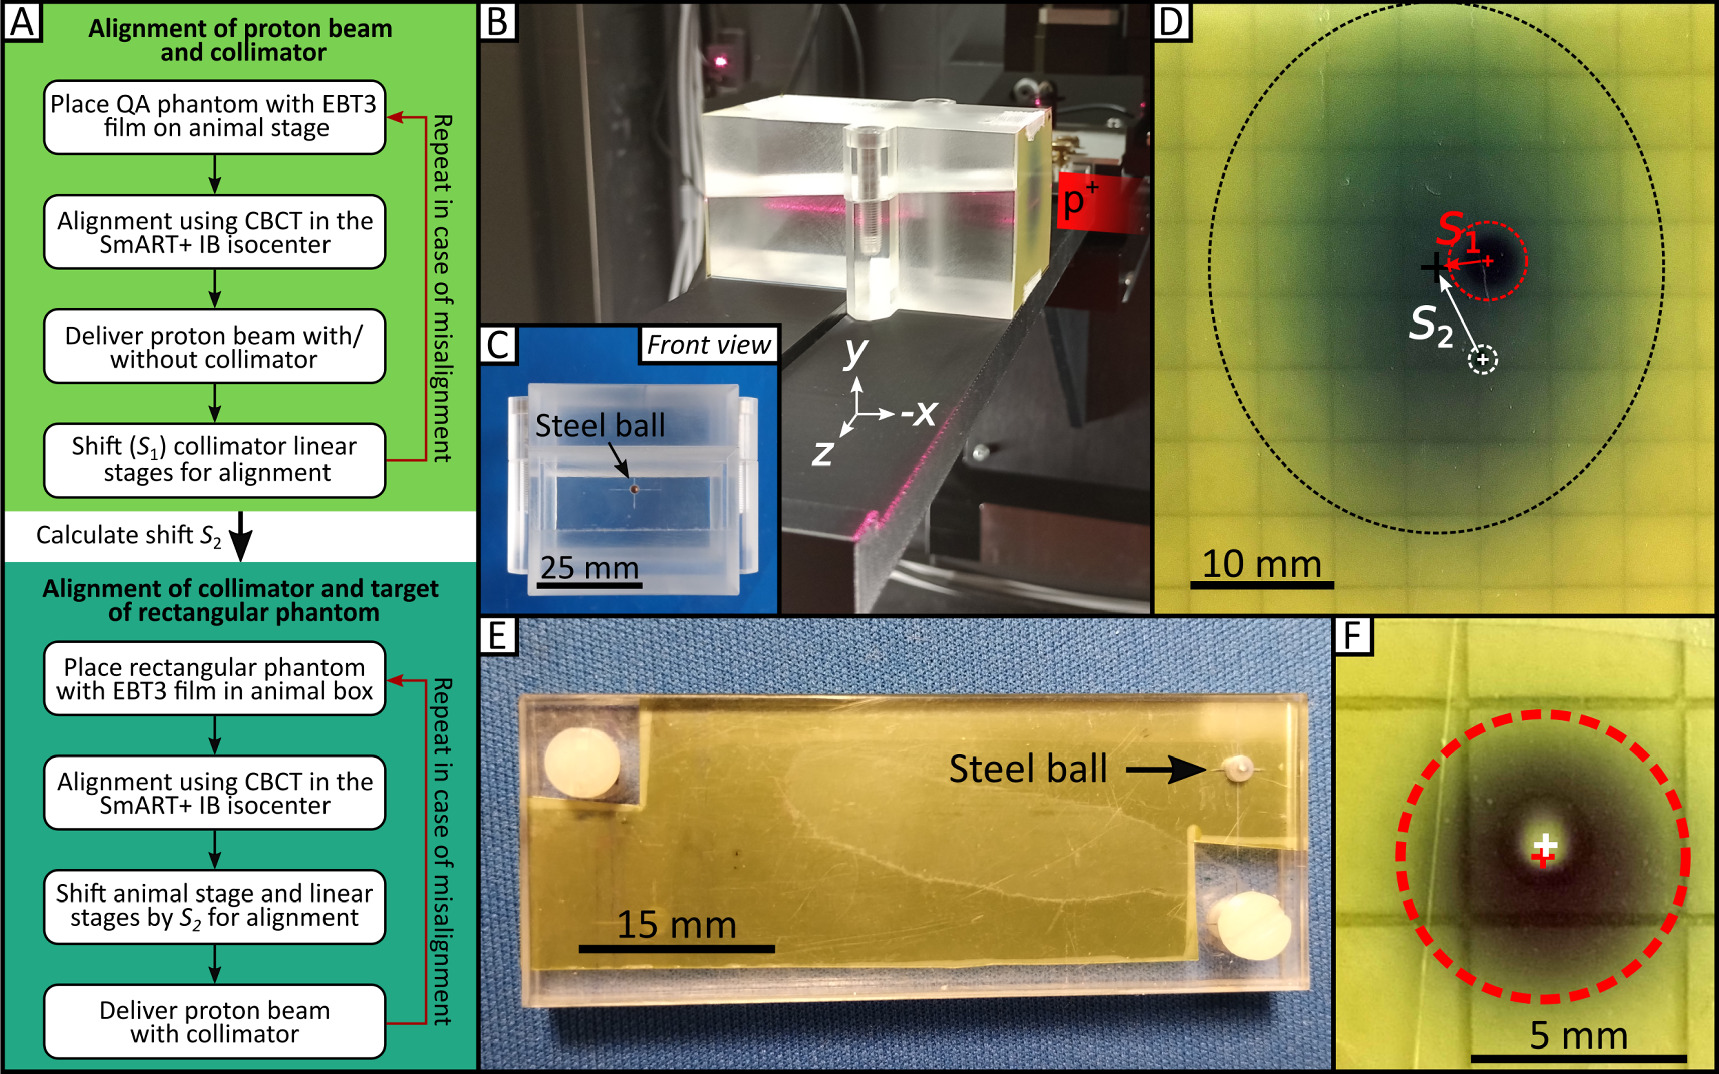

A QA protocol (figure 7(A)) to be followed before each experiment is implemented for successful alignment of the collimated proton beam and the SmART+ IB isocenter using a custom-made QA phantom (50 mm × 50 mm × 87 mm) constructed from PMMA, as illustrated in figures 7(B)/(C).

Figure 7. QA procedure and phantoms for SAPPHIRE. (A) QA procedure to align proton beam, collimator and mouse target. The QA protocol consists of two steps, the first being the alignment of the proton beam with the collimator, followed by the alignment of the collimated proton beam with the target of the rectangular phantom. (B) QA phantom with attached EBT3 film placed on the animal stage, with the proton beam coming from the right side. The 5° inclined cut can be seen throughout the phantom. (C) Front view of the PMMA QA phantom (50 mm × 50 mm × 87 mm) with the steel ball in the center, which is used as target in the CBCT. (D) Irradiated EBT3 film with the uncollimated beam spot (black dashed circle), the collimated beam spot (red dashed circle) and the marked target (white dashed circle) before alignment. (E) Rectangular phantom used for the daily QA routine. It houses an EBT3 radiochromic film and a steel ball. (F) After correct alignment involving the steel ball as the target, accurate irradiation results in a black patch (indicating dose absorption on the EBT3 film; represented by the dashed red circle) with a non-darkened area at the center (indicating the dose spared by the steel ball) with a deviation of <0.35 mm.

Standard image High-resolution imageFor the alignment of proton beam and collimator, the SmART+ IB is positioned in front of the proton beamline with the small proton beam window facing the beamline (figure 1). The QA phantom for collimator alignment is placed on to the animal stage as shown in figure 7(B). This phantom features a specially designed edge at the bottom for secure placement on the adapter. At the center of the phantom's surface facing the beam, a small steel ball with a 2 mm diameter is embedded to serve as the target for the QA procedure. EBT3 films can be placed on the same side of the phantom as the steel ball and within a 5° inclined cut trough the phantom for lateral beam profile and depth dose profile measurements, inspired from the work of Kim et al (2019). It must be ensured that the QA phantom is targeted by the proton beam when it is positioned at the SmART+ IB isocenter by using the integrated room laser system. A new EBT3 film is positioned on the front side of the phantom (note that the collimator holding the range shifter is not yet placed in the beam path). Afterwards, the proton beam window and the opposite door are closed, and a CBCT of the QA phantom is acquired using the 60 kV, 0.5 mA imaging protocol. The animal stage coordinates are  . The center of the steel ball (target) is identified in the CBCT, and the animal stage is then moved to position the steel ball in the isocenter resulting in new stage coordinates

. The center of the steel ball (target) is identified in the CBCT, and the animal stage is then moved to position the steel ball in the isocenter resulting in new stage coordinates  . Next, with the proton beam window and door opened again, a proton beam is delivered using 90 MeV, 0.1 nA for 17 s to produce an image of the beam spot (figure 7(D), black dashed circle). The collimator, along with the PMMA range shifter, is then introduced into the beam path, directly in front of the QA phantom with collimator axis coordinates

. Next, with the proton beam window and door opened again, a proton beam is delivered using 90 MeV, 0.1 nA for 17 s to produce an image of the beam spot (figure 7(D), black dashed circle). The collimator, along with the PMMA range shifter, is then introduced into the beam path, directly in front of the QA phantom with collimator axis coordinates  . A second proton beam is delivered using 90 MeV, 0.1 nA for 80 s (figure 7(D), red dashed circle). The position of the steel ball is marked with a pen on the film (figure 7(D), white dashed circle), and the film is scanned using the flatbed scanner. The shift S1 between the center of the two dark patches from the proton beam is measured using Fiji ImageJ (version v1.53n, 64-bit Windows, Schindelin et al (2012)). Based on this, the collimator linear stages are adjusted, and the new coordinates

. A second proton beam is delivered using 90 MeV, 0.1 nA for 80 s (figure 7(D), red dashed circle). The position of the steel ball is marked with a pen on the film (figure 7(D), white dashed circle), and the film is scanned using the flatbed scanner. The shift S1 between the center of the two dark patches from the proton beam is measured using Fiji ImageJ (version v1.53n, 64-bit Windows, Schindelin et al (2012)). Based on this, the collimator linear stages are adjusted, and the new coordinates  are recorded, ensuring that the collimator is now aligned with the proton beam. To verify the alignment of the proton beam and collimator, the procedure is repeated. The shift S2 between the proton beam spot without the collimator and the marked (isocenter) position of the QA phantom's steel ball is also determined from the EBT3 film.

are recorded, ensuring that the collimator is now aligned with the proton beam. To verify the alignment of the proton beam and collimator, the procedure is repeated. The shift S2 between the proton beam spot without the collimator and the marked (isocenter) position of the QA phantom's steel ball is also determined from the EBT3 film.

In order to align the collimated proton beam with the target for irradiation (steel ball), the rectangular phantom is used, as shown in figure 7(E). The steel ball of the rectangular phantom is located between two plastic plates, with an EBT3 film placed directly behind it. With the rectangular phantom in the animal box, a CBCT is acquired using the same imaging parameters as before. The center of the steel ball within the CBCT is used as target position and moved to the isocenter, resulting in new stage coordinates  . Then, the animal stage is shifted by S2, and the collimator stages are shifted by −S2 and the difference between P2 and P3. With accurate execution, the proton beam, collimator, and steel ball are now properly aligned. The result in figure 7(F) is obtained after delivering another proton beam using 90 MeV, 0.1 nA for 50 s, yielding a black patch (indicating dose on the EBT3 film) with an unexposed spot in the center (representing the dose spared by the ball). The deviation of the target from the actually irradiated spot is in this case <0.35 mm.

. Then, the animal stage is shifted by S2, and the collimator stages are shifted by −S2 and the difference between P2 and P3. With accurate execution, the proton beam, collimator, and steel ball are now properly aligned. The result in figure 7(F) is obtained after delivering another proton beam using 90 MeV, 0.1 nA for 50 s, yielding a black patch (indicating dose on the EBT3 film) with an unexposed spot in the center (representing the dose spared by the ball). The deviation of the target from the actually irradiated spot is in this case <0.35 mm.

For multi-day mouse experiments, the SAPPHIRE alignment procedure of proton beam and collimator takes approximately 45 min and needs to be performed once per beam time, whereas the verification with the rectangular phantom should be conducted every morning prior to the initial animal irradiation. The targeting steps for the irradiation of mice will be identical to those of the rectangular phantom, targeting an anatomical structure instead of the steel ball.

Additionally, a QA protocol was developed to ensure robust, precise, and consistent alignment of all components for proton irradiation. The custom-made QA phantoms with an embedded steel ball serve as a reliable target for alignment verification. The system demonstrates a targeting accuracy of <0.35 mm, placing it on par with other small animal irradiators (Tillner et al 2014, 2016, Kim et al 2019, Schneider et al 2022). This level of precision proves adequate for a multitude of small animal experiments, considering the inherent difficulty in achieving precise animal positioning. The QA alignment procedure needs to be tested more often to monitor and improve its accuracy, as it had only been performed once. An automated method of alignment could involve the use of a Lynx detector (IBA Dosimetry, Schwarzenbruck, Germany) instead of EBT3 films with online evaluation of beam spot positions.